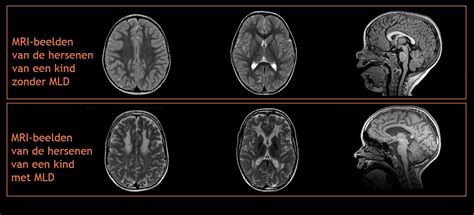

Bij vage, aanhoudende en onverklaarde symptomen, of bij symptomen die specifiek wijzen op een hersenprobleem, wordt een hersenscan uitgevoerd. Bij voorkeur wordt een MRI-scan (magnetic resonance imaging) gebruikt, omdat deze de hersenen gedetailleerd in beeld brengt met behulp van een magnetisch veld en radiogolven. Als een MRI-scan niet direct beschikbaar is en het onderzoek dringend is (bijvoorbeeld bij plotselinge achteruitgang), wordt een CT-scan (computertomografie) uitgevoerd. Deze is sneller, maar toont de hersenen minder gedetailleerd en maakt gebruik van röntgenstralen.